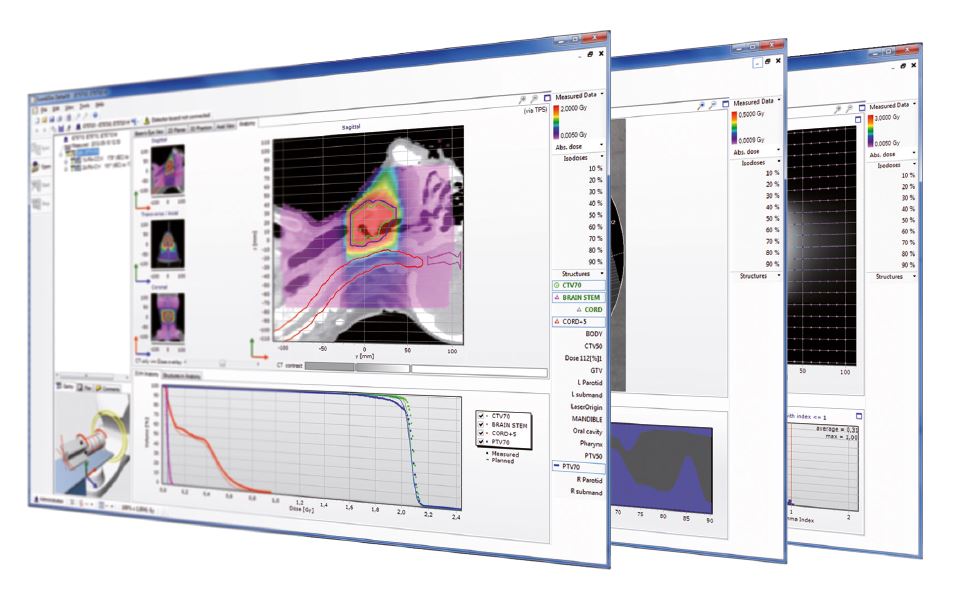

Delta4 software

Streamline your workflow

Delta4 software

Instant and accurate analysis

- Isocentric measurements in two orthogonal detector planes

- 1069 p-type silicon diodes

- Resolution 5 mm at isocenter, can be increased to 2.5 mm by merging

- Measures where it matters

Delta4 Software

Instant Results